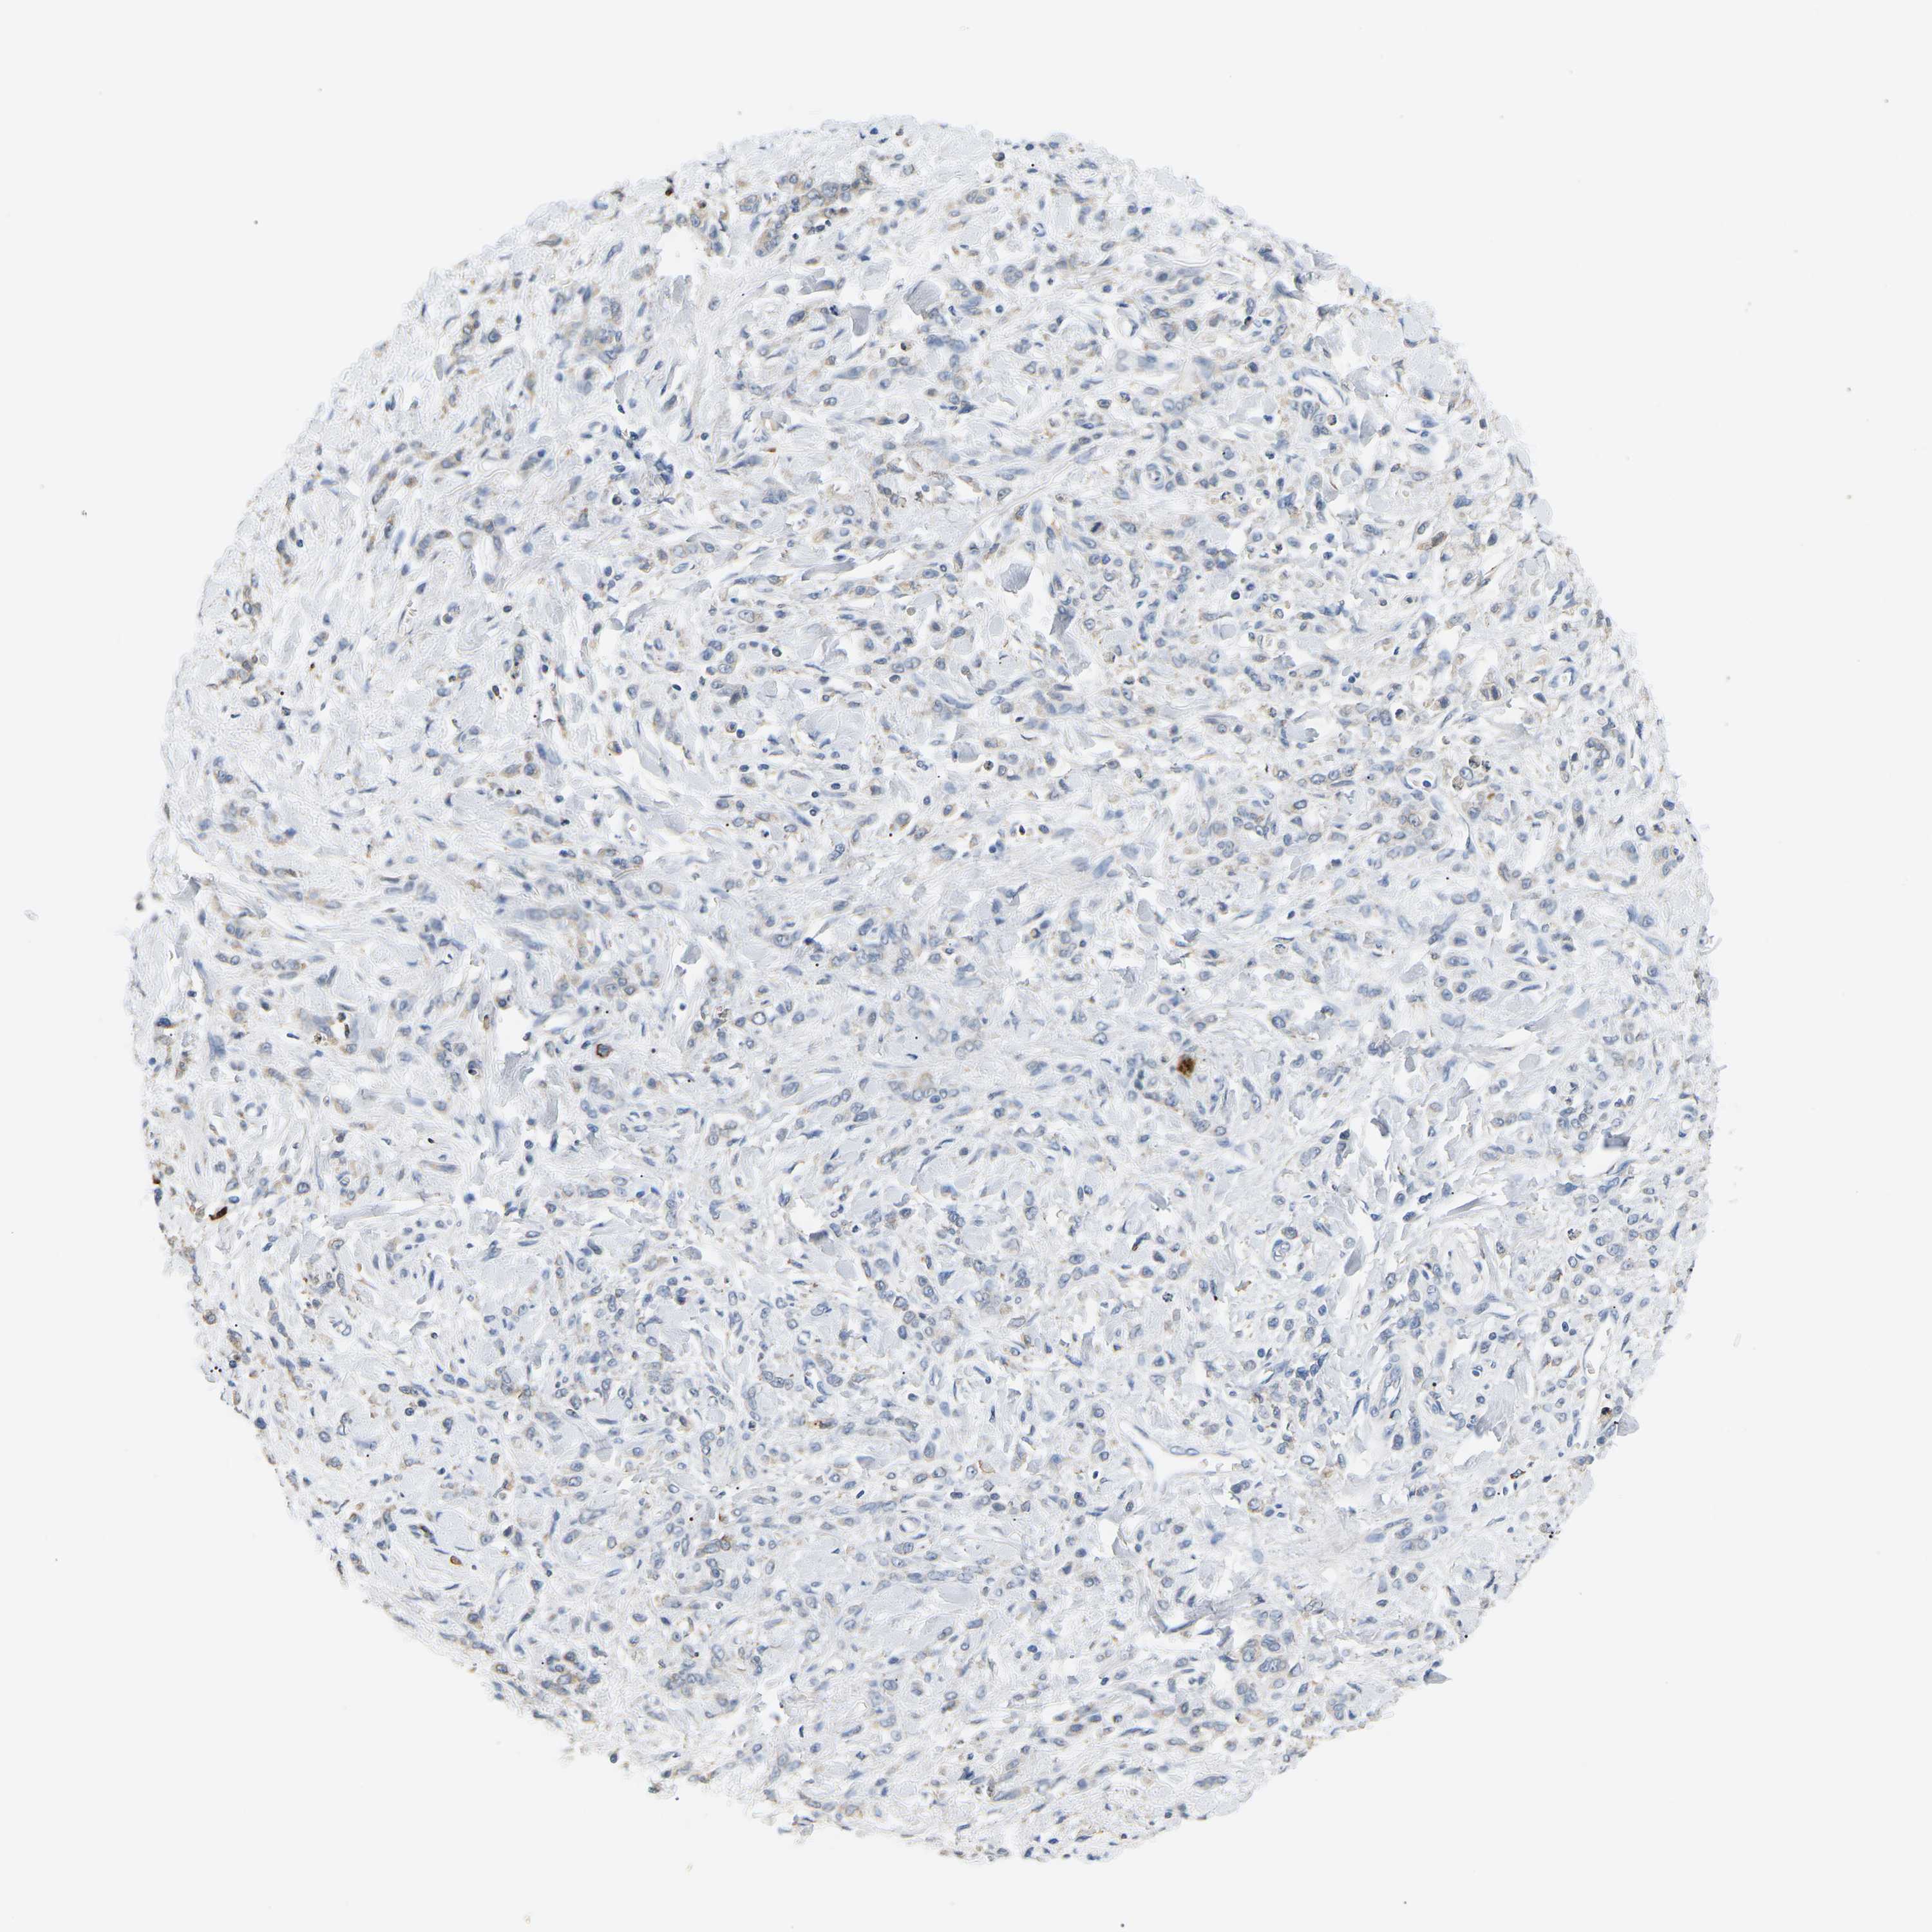

STOMACH CANCER - Protein expressioni

A mouse-over function shows sample information and annotation data. Click on an image to view it in a full screen mode. Samples can be filtered based on level of antibody staining by selecting one or several of the following categories: high, medium, low and not detected. The assay and annotation is described here.

Note that samples used for immunohistochemistry by the Human Protein Atlas do not correspond to samples in the TCGA dataset.

Antibody stainingi

Antibody staining in the annotated cell types in the current human tissue is reported as not detected, low, medium, or high, based on conventional immunohistochemistry profiling in selected tissues. This score is based on the combination of the staining intensity and fraction of stained cells.

Each image is clickable and will lead to virtual microscopy that enables deeper exploration of all samples and also displays staining intensity scores, fraction scores and subcellular localization as well as patient and tissue information for each sample.

Antibody HPA068955

Antibody CAB016075

Staining

High

Medium

Low

Not detected

Intensity

Strong

Moderate

Weak

Negative

Quantity

>75%

75%-25%

<25%

None

Location

Nuclear

Cytoplasmic/membranous

Cytoplasmic/membranous,nuclear

Adenocarcinoma, NOS

Adenocarcinoma, High grade